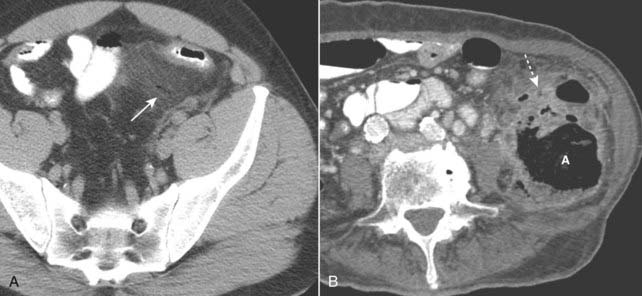

Figure 18-14 Diverticulitis, CT.

A, Infiltration of the pericolonic fat is demonstrated by a hazy increase in attenuation (solid white arrow) of the normal fat. Focal infiltration of fat is a common characteristic of inflammatory disease. B, There is a large abscess cavity (A) in the left lower quadrant in this close-up of a CT scan of the lower abdomen. There are adjacent small bubbles of gas that are not contained within the bowel and infiltration of the normal fat (dotted white arrow). These findings are secondary to a confined perforation with abscess formation from diverticulitis.